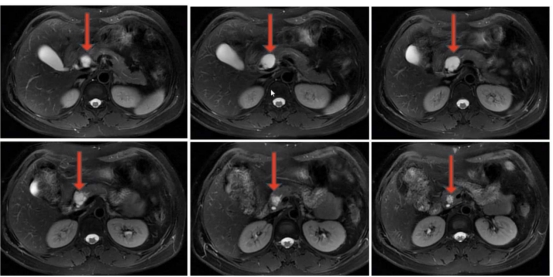

該患者體檢時發(fā)現(xiàn)胰腺囊性占位,因擔心外科手術創(chuàng)傷��,遲遲未敢治療���,隨著囊腫逐漸增大,出現(xiàn)了反復腹痛癥狀��。來到衡陽市中心醫(yī)院消化內科就診后,醫(yī)生團隊為其完善超聲內鏡及囊液分析等檢查�,明確診斷為胰腺粘液性囊腫,排除禁忌證后實施了聚桂醇滅活術���。術后患者腹痛癥狀即刻緩解����,住院3天便順利出院��,復查時囊腫體積已明顯縮小����,生活質量完全恢復正常。

胰腺作為人體消化系統(tǒng)的“核心引擎”�,深藏于腹腔深處,其病變往往隱匿難察�,治療難度頗高。胰腺囊性占位是臨床常見的胰腺病變�,涵蓋假性囊腫、囊性腫瘤等多種類型�����,部分病變存在癌變風險�,或因體積增大壓迫周圍器官引發(fā)腹痛��、腹脹等不適�����,嚴重影響患者生活質量�。以往傳統(tǒng)治療多依賴外科手術�����,創(chuàng)傷大��、恢復慢���,且可能伴隨胰漏����、出血等并發(fā)癥����,患者顧慮很多。現(xiàn)在��,衡陽市中心醫(yī)院消化內科團隊推出超聲內鏡(EUS)引導下胰腺囊性占位聚桂醇滅活術���,為患者帶來精準����、安全����、高效的診療新選擇。該技術“超級微創(chuàng)”�,將超聲內鏡的“精準導航”與聚桂醇的“溫和消融”完美結合,適用于直徑>1cm�、有癥狀的胰腺囊性病變,以及高齡�、合并基礎疾病無法耐受外科手術或拒絕手術的患者。手術全程在超聲內鏡實時引導下進行����,醫(yī)生可清晰洞察病灶位置、大小及與周圍血管��、器官的解剖關系����,通過細針穿刺精準穿刺至囊腔內,抽凈囊液后注入聚桂醇硬化劑,實現(xiàn)對病灶的靶向滅活�。整個手術僅需30分鐘左右,全程微創(chuàng)�����,無需開腹����,僅留下細微穿刺痕跡,有效避免了傳統(tǒng)手術對胰腺及周圍組織的損傷�,最大程度保留胰腺正常生理功能。

聚桂醇滅活術是消化介入領域的前沿技術�����,憑借其安全性高�、不良反應少的優(yōu)勢,逐步取代傳統(tǒng)消融劑成為囊性病變治療的優(yōu)選方案�����。與傳統(tǒng)無水乙醇消融相比�����,聚桂醇通過改變細胞膜表面能量分布,破壞囊壁內皮細胞�����,引發(fā)無菌性炎癥及纖維組織增生��,最終實現(xiàn)囊腔閉合�,不僅消融效果確切����,且術后腹痛、醉酒樣反應等不良反應發(fā)生率極低�,總體并發(fā)癥發(fā)生率僅4.3%,顯著提升了治療的安全性與患者耐受性�。臨床研究顯示,該技術總體消融有效率高達94.7%�,隨訪12個月以上的長期有效率亦達79.4%。